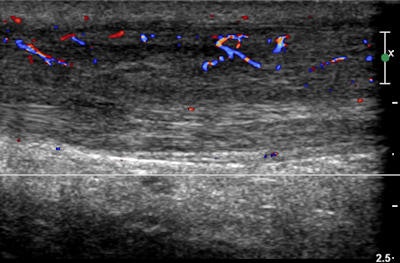

- Hurdler with an inversion ankle injury. Color flow ultrasound showed a grade 2 partial tear of the anterior talofibular ligament.